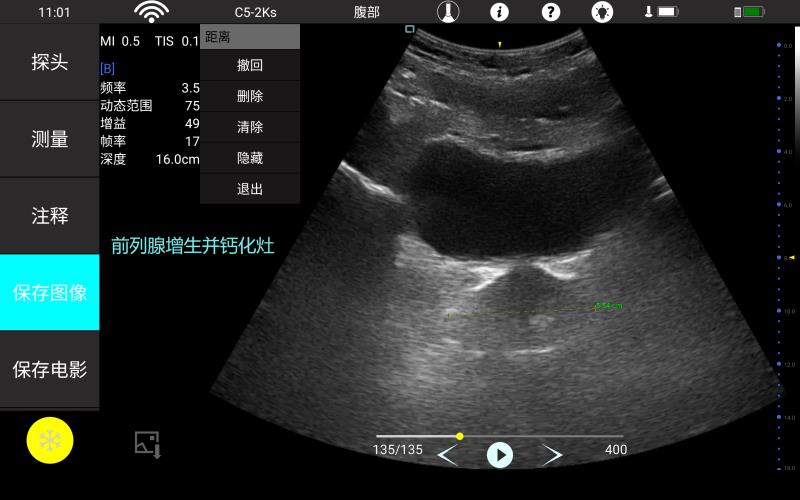

腹部

肾脏